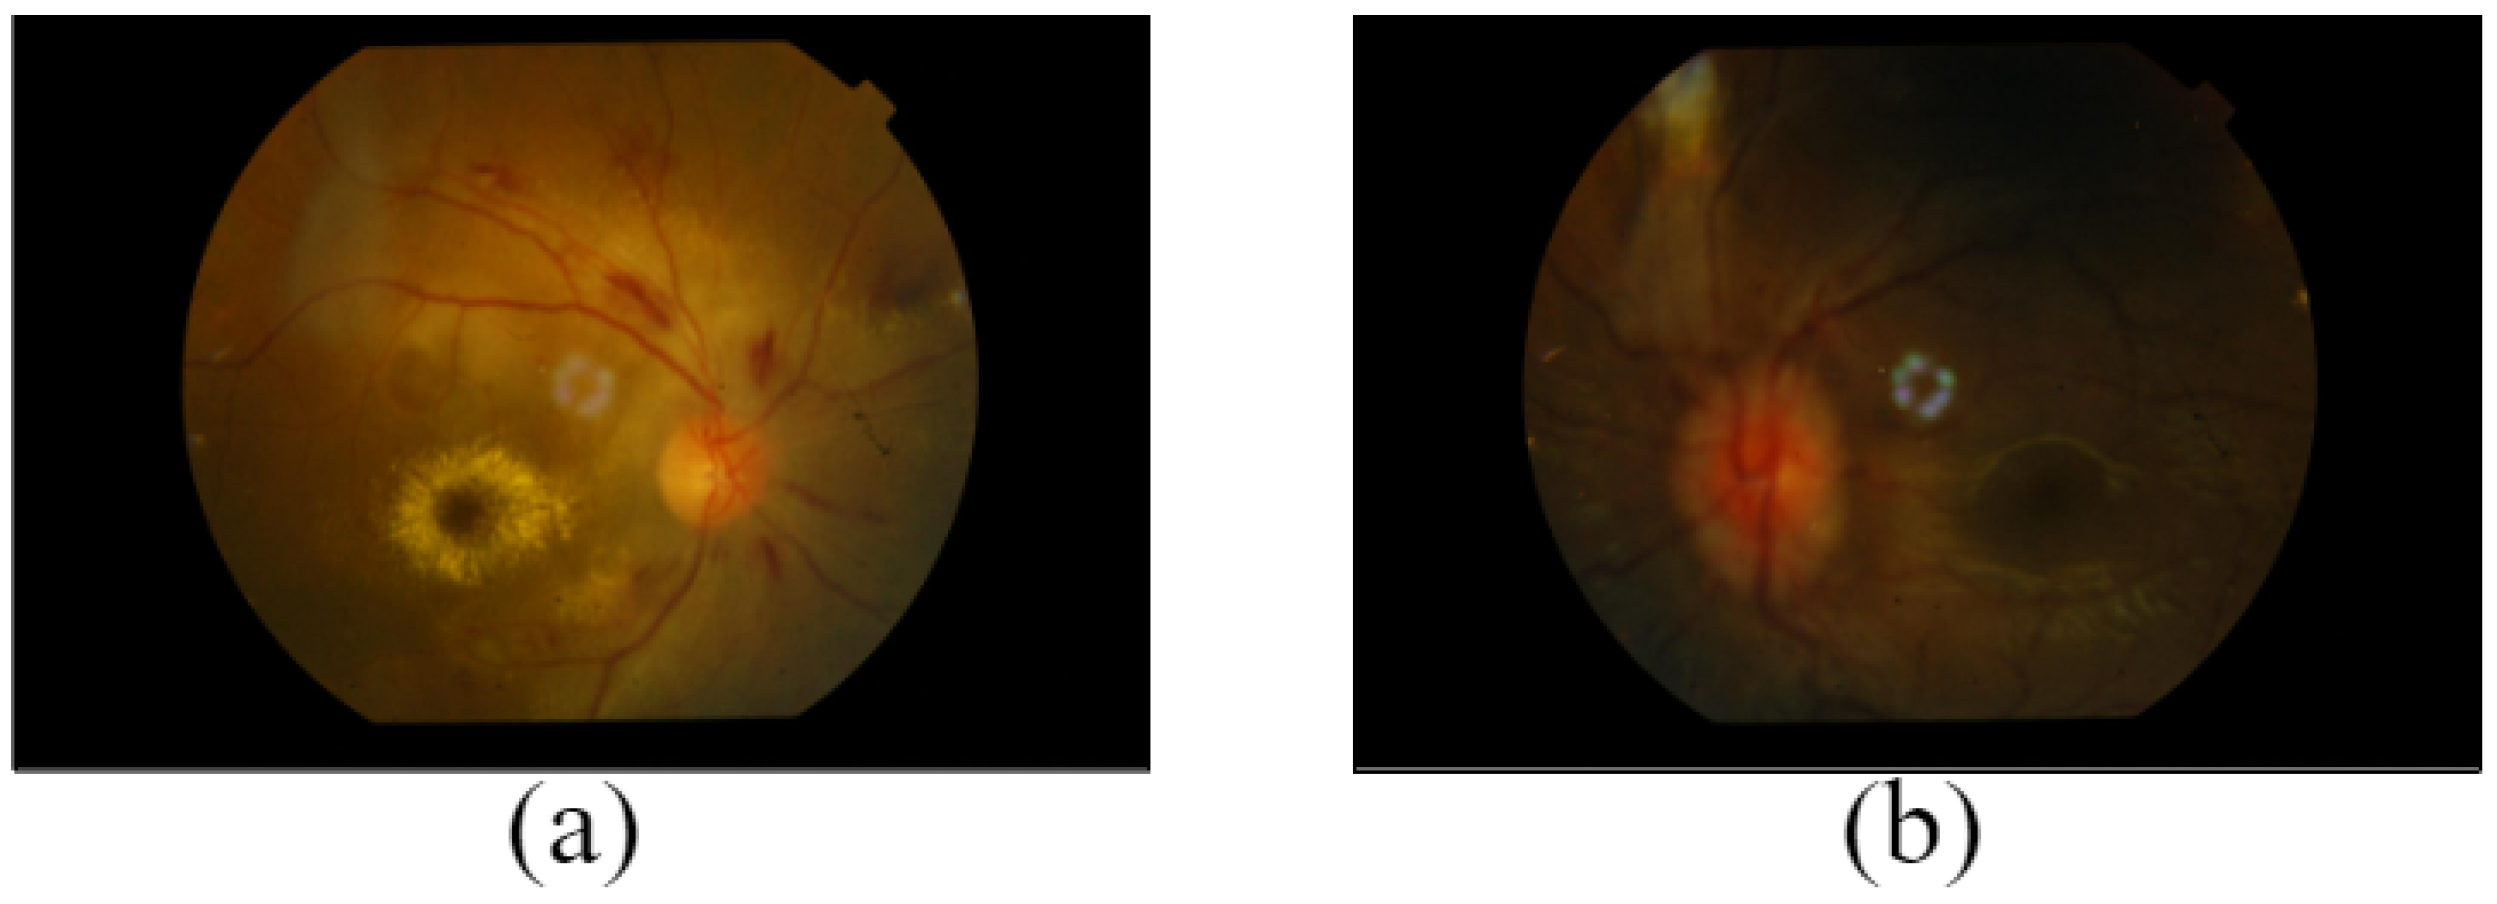

Asteroid Hyalosis (AH): AH is the typical ophthalmologist finding. Asteroid hyalinosis (AH) is observed as yellow–white dazzling, reflecting particles enclosed by densely adhered fibrils [16]. It is necessary to conduct an accurate ocular evaluation to diagnose this illness as shown in Figure 2a.

Figure 2.

Images of (a) Asteroid Hyalosis (AH), (b) Anterior ischemic optic neuropathy (AION), and (c) Age-Related Macular Degeneration (ARMD).

Anterior Ischemic Optic Neuropathy (AION): The optic nerve’s swollen and pale presence is observed on the retina. Moreover, there are retinal cotton wool spots at the anterior pole, and this artery can cause temporary central retinal artery occlusion. Ischemic optic neuropathies (IONs) are the most frequent acute optic neuropathy in patients older than 50. The signs of AION are reduced clarity of vision, color blindness, and other visual defects [17,18]. Figure 2b shows an image of AION.

Age-Related Macular Degeneration (ARMD): ARMD is one of the leading causes of significant vision loss, including vision impairment, among the population, usually occurring in those over 60. Lipoprotein deposits and acellular wastes are responsible for drusen. Retinal pigment epithelium abnormalities, drusen, and choroidal neovascular membrane formation are referred to as ARMD. The presence of visible spots of degeneration in the retinal fundus images is used to identify the ARMD as shown in Figure 2c [19,20,21]. Furthermore, geographic atrophy and drusen that extend to the macula center are indications of advanced non-neovascular age-related macular degeneration [22].